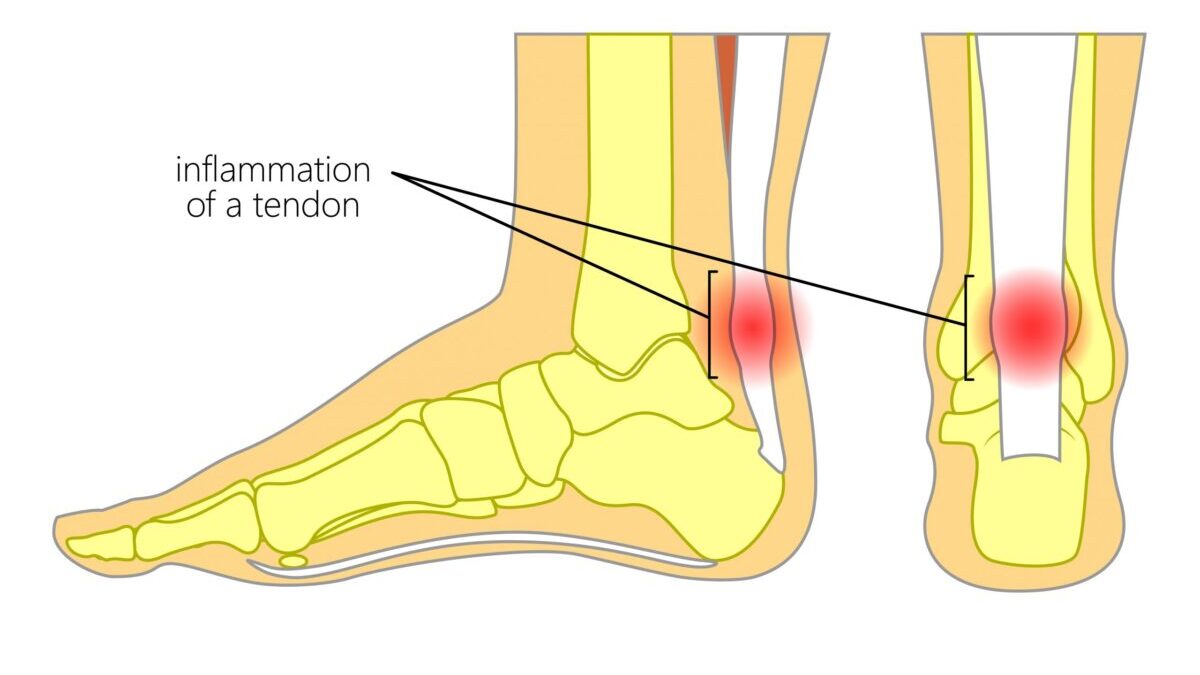

Achilles tendinitis

Achilles tendinitis is a common condition that occurs when the large tendon that runs down the back of the lower leg becomes irritated and inflamed.

The Achilles tendon is the largest tendon in the body. It connects the calf muscles to the heel bone and is used when you walk, run, climb stairs, jump, and stand on your tip toes. Although the Achilles tendon can withstand great stresses from running and jumping, it is also prone to tendinitis, a condition associated with overuse.

Tendinitis is inflammation of a tendon. Inflammation is the body's natural response to injury and often causes swelling, pain, or irritation.

Achilles tendinitis is different than an Achilles rupture, a condition where the tendon becomes separated off the heel bone or completely torn in half.

Achilles tendinitis is typically not related to a specific injury. The problem results from repetitive stress to the tendon. This often happens when we push our bodies to do too much, too quickly.